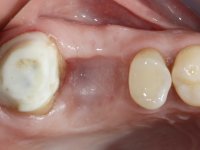

Teeth 17 and 16 were prepared for the fabrication of a 2-element Zr bridge. The impression was performed with a double mixing technique and a monolithic bridge in Zr was made in the laboratory. 4 years later, an abscess appeared in the apical area of tooth 26. It was decided to remove the bridge, remove the intra-radicular posts and retract the endodontic treatments of teeth 17 and 16. The removal of the bridge was carried out by making two cervical cavities. in the palatal area of the bridge and with a microluxator, disinsertion movements were performed. The intra-radicular posts were removed using fine drills and an ultrasound tip. The bridge was provisionally cemented and the patient was referred to a fellow endodontist for endodontic retreatment. After the retreatment, the intraradicular posts were placed again and the bridge was definitively cemented. One year later, a new abscess appears, possibly related to a root fracture. The bridge was sectioned between tooth 27 and 26 and tooth 26 was extracted and the crown of 27 was provisionally cemented. 3 months later, teeth 27 and 25 were prepared and a temporary bridge was made in dual polymerization resin. Then, an impression was made using the double mixing technique and a 3-element bridge in Zr was made in the laboratory. It was permanently cemented in the mouth with resin-reinforced glass ionomer cement.